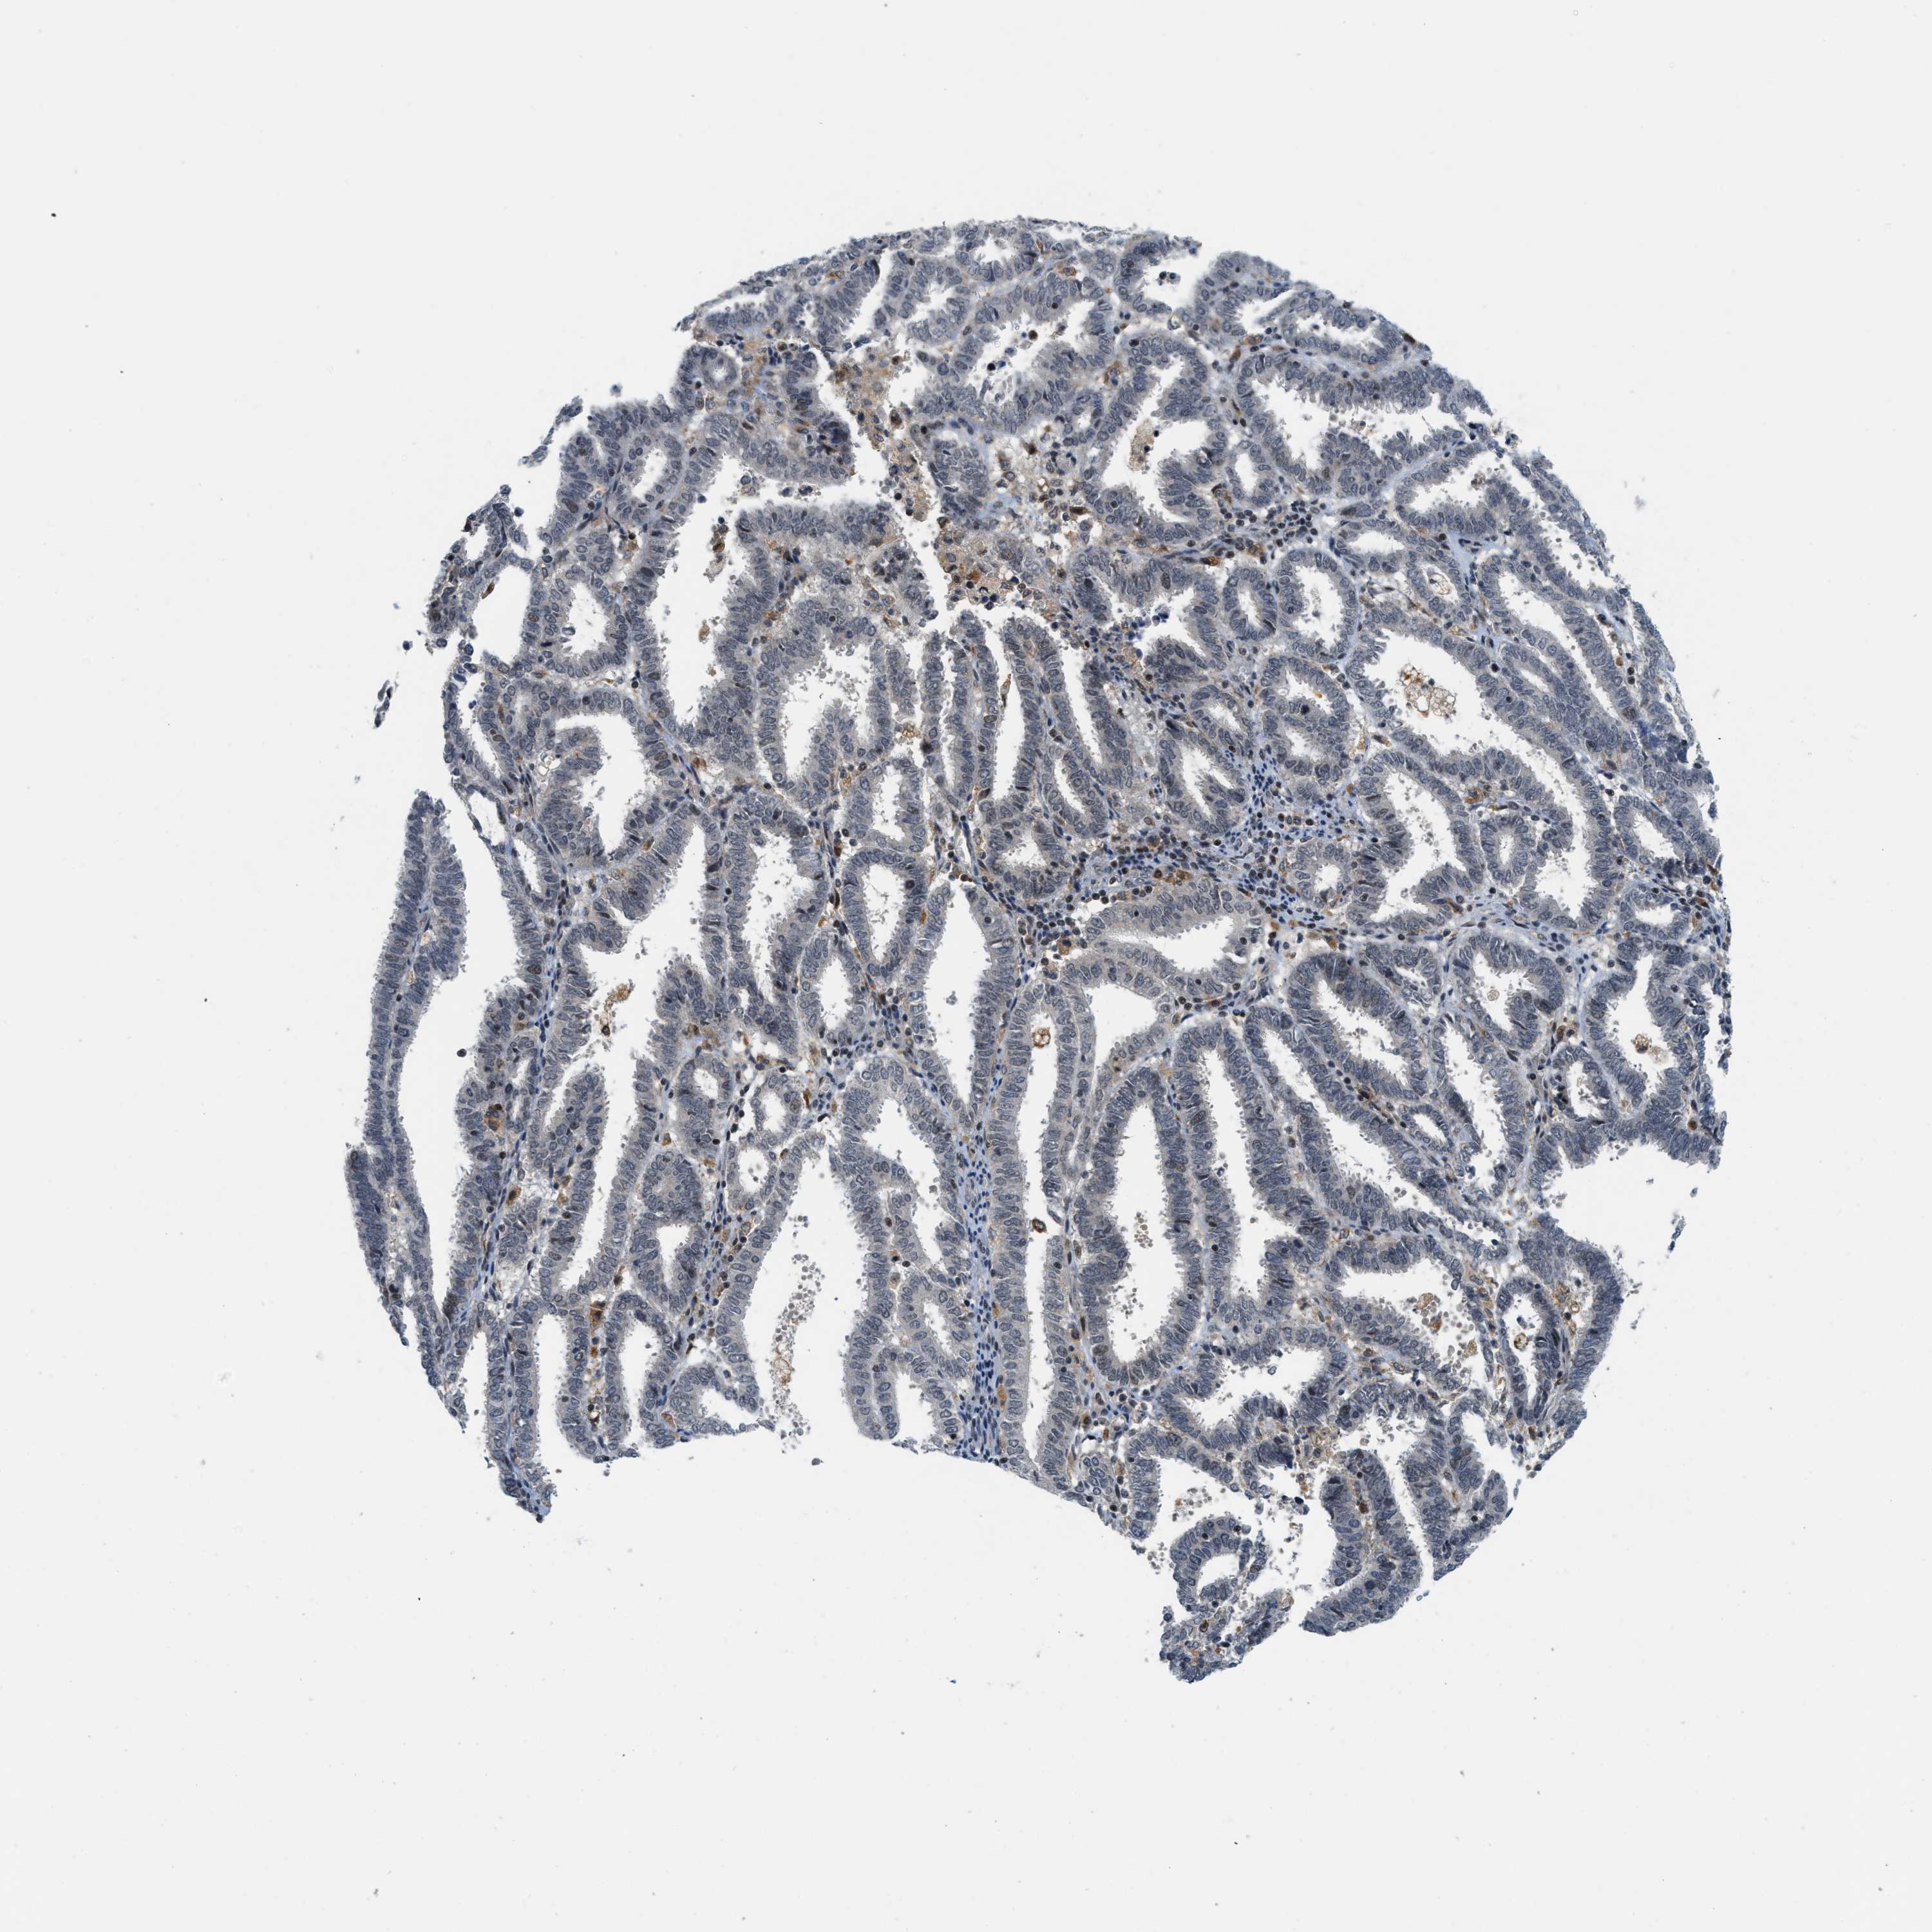

ENDOMETRIAL CANCER - Protein expressioni

A mouse-over function shows sample information and annotation data. Click on an image to view it in a full screen mode. Samples can be filtered based on level of antibody staining by selecting one or several of the following categories: high, medium, low and not detected. The assay and annotation is described here.

Note that samples used for immunohistochemistry by the Human Protein Atlas do not correspond to samples in the TCGA dataset.

Antibody stainingi

Antibody staining in the annotated cell types in the current human tissue is reported as not detected, low, medium, or high, based on conventional immunohistochemistry profiling in selected tissues. This score is based on the combination of the staining intensity and fraction of stained cells.

Each image is clickable and will lead to virtual microscopy that enables deeper exploration of all samples and also displays staining intensity scores, fraction scores and subcellular localization as well as patient and tissue information for each sample.

Antibody CAB016136

Antibody CAB017773

Staining

High

Medium

Low

Not detected

Intensity

Strong

Moderate

Weak

Negative

Quantity

>75%

75%-25%

<25%

None

Location

Nuclear

Cytoplasmic/membranous

Cytoplasmic/membranous,nuclear

Adenocarcinoma, NOS